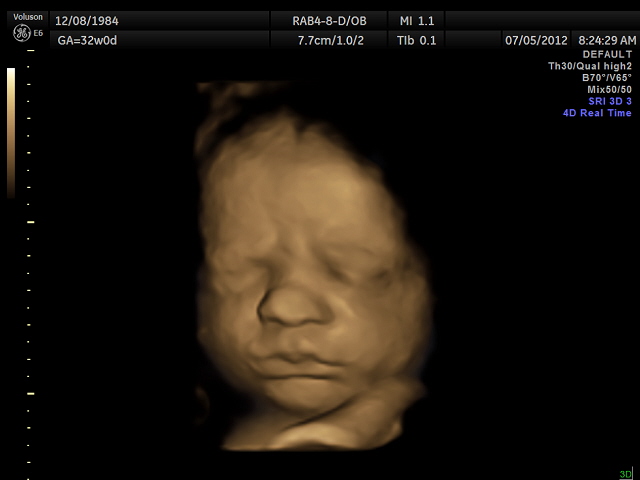

Shanan Lee Reynolds 12-8-1984

And here YOU are!!!!

SAWYER MADDOX LEITH

4D ULTRASOUND

I want you to know that I have thoroughly enjoyed all LONG nine months of my pregnancy with you. We found out that we were having a baby on Christmas Eve 2011 right after church! What an incredible Christmas gift, nothing else will ever compare!! Your daddy and I have been totally amazed with this whole process and have both enjoyed watching you grow inside of me. God is so good! It has been remarkable hearing your tiny heart beat and watching you move around inside of me.....it is beyond amazing! When we saw your little face on 4D ultrasound you instantly melted my heart. I’m thinking that you may favor your mommy more – yay! But I’m so so sorry son, I think that you may have your daddy’s feet :) You have already brought your daddy and I so much joy and closer as husband and wife - we cannot wait to become a “family of three.” We have tried to prepare for you as best as we know how and have read the “best of the best” parenting books, bought all of the “latest and greatest” gadgets and clothing and prepared what we feel is “the perfect nursery” all we are missing now is you! Although there are not many “things” that you don’t have, life isn’t about “things” I hope to teach you that as soon as you are able to comprehend it all - Life is about love and what you can do to help others.